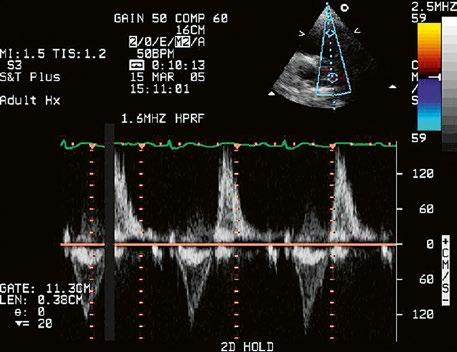

Obr. 45.44 Pacientka s těžkou, dlouhodobě neřešenou valvární a subvalvární stenózou plicnice (také Obr. 45.45 ) s extrémně těžkou hypertrofií přední stěny pravé komory (označena zelenými křížky a šipkou, šíře stěny PK18 mm). Hypertrofie myokardu infundibula přispívá k sekundární subvalvární stenóze plicnice. M mode, parasternální dlouhá osa.

AO – aorta, LK – levá komora, LS – levá síň, PK – pravá komora

Obr. 45.45 Těžká, dlouhodobě neřešená valvární a subvalvární stenóza plicnice s vysokým gradientem 155/82 mmHg (CW doppler) (viz též Obr. 45.44)